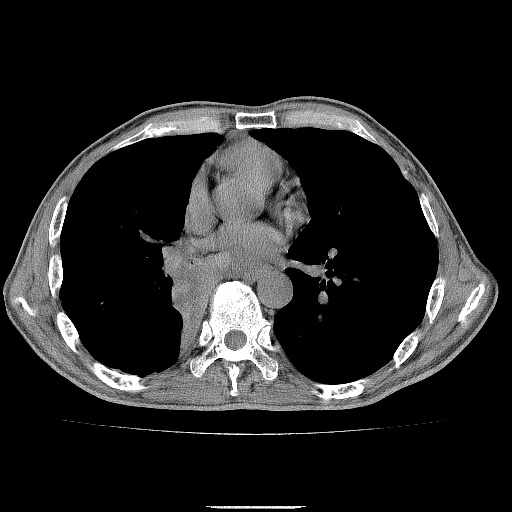

男性患者,63岁。右侧胸背部疼痛2月,加重一周。

考虑:右肺中央型肺癌并右肺下叶不张;两肺尖继发性肺结核。

还有纵隔多处肿大淋巴结及肋骨的改变、两肺多发结节灶。

考虑右中心型肺癌并右下肺不张,肺及纵隔,左肋骨转移。

右肺下叶支气管狭窄闭塞,右下肺不张,气管前间隙淋巴结肿大,两上肺散在分部粟粒灶,沿肺血管支气管束分部,血管支气管束走形较为光滑。考虑右肺中心型肺癌合并肺不张,纵隔淋巴结转移,两上肺癌性淋巴管炎

右肺下叶中心性肺癌并纵隔淋巴结转移,左侧肋骨转移。双肺上叶继发性结核表现。

1)右肺下叶中心性肺癌并纵隔淋巴结转移,两肺转移,左侧肋骨转移。2)双肺上叶继发性结核。

右肺下叶中心性肺癌并纵隔淋巴结及两肺、左侧肋骨转移。双肺上叶继发性结核表现。